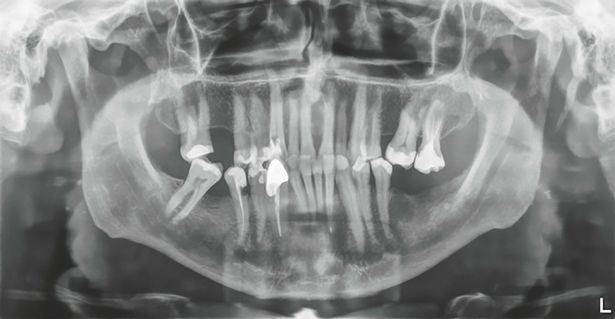

Selepas melakukan pemeriksaan X-ray, Dr Lukas tidak menyangka ia akan mempunyai panjang sedemikian.

Terdapat jangkitan pada sekitar gigi terbabit, membuatkan Dr Lukas tidak punyai pilihan lain selain mencabut ia keluar.